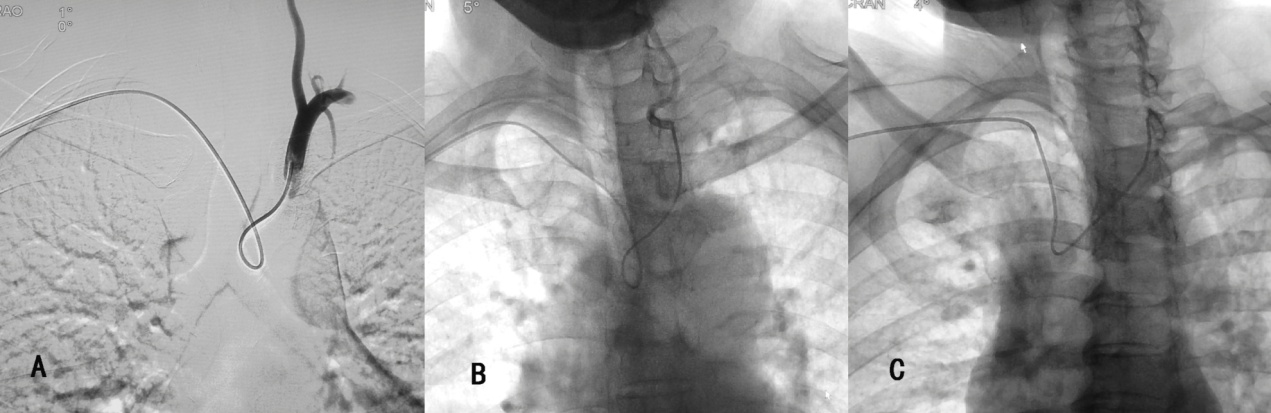

因此, 需使用西蒙管的反勾技术(使导管扭曲呈“8”字形而不是导管原塑性的形状,使得导管末端的方向朝上)才能实现血管的超选(图5),这造成导管的操作困难

理想的导管应该是拥有合适的外形,在操作时能简化操作步骤;具有恰当的尺寸,在狭小的空间内游刃有余。 (图C)

如能设计一种专门针对从桡动脉入路可简单、快捷行脑血管造影用的导管则可有效的解决这一难题。